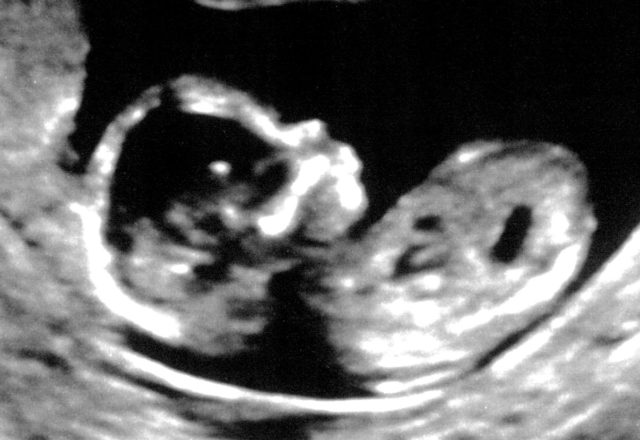

First Ultrasound

Posted on June 21, 2016July 24, 2016 By Stephen